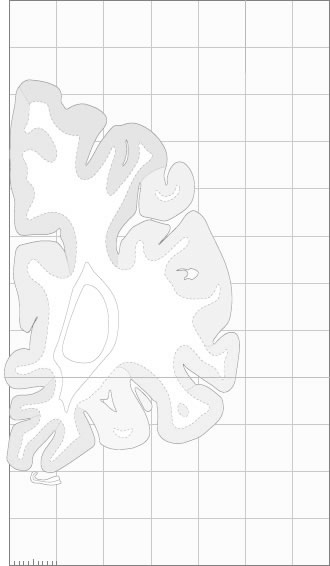

Frontal sections (Nissl) from the Atlas Brain:

Macroscopy

Schematic

Slice ID:

r1-0050

Plate NR:

05

Position:

-34,5 mm